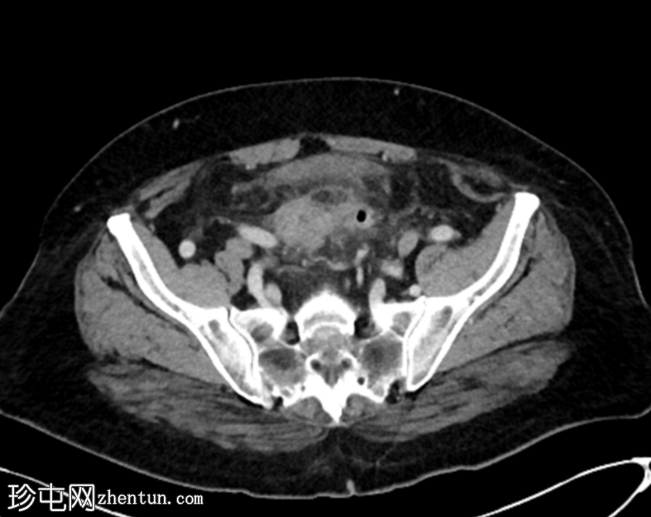

轴位增强扫描(门静脉期)

多发性乙状结肠憩室。

乙状结肠壁增厚,伴结肠周围脂肪条索影,左侧壁局部穿孔。未见肠外脓肿、腹水或气腹,提示IA期复杂性急性憩室炎。

脂肪肝。

胆囊切除术夹。

双侧肾盂周围及皮质囊肿,左侧较大。